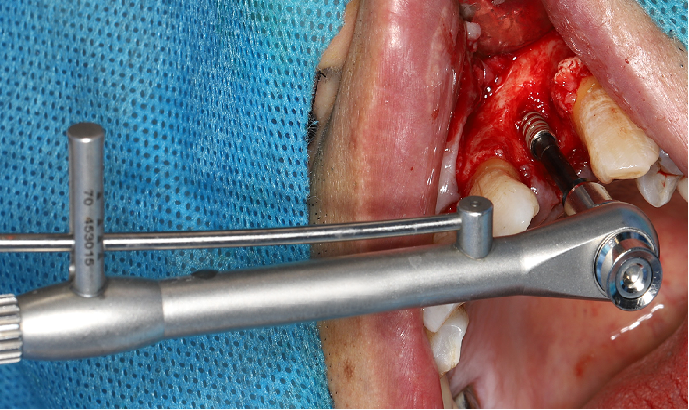

五、标准种植外科备洞程序

使用球钻定位,逐级备孔。

完成备洞。

旋入种植体,初期稳定性为 30N。

直接上愈合基台。